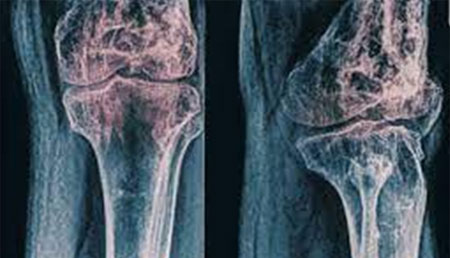

Estudio PRORADIUM: Evaluación de biomarcadores del metabolismo óseo y supervivencia en pacientes con cáncer de próstata metastásico.

La Dra. Nuria Romero-Laorden, profesora asociada de la cátedra, ha publicado un artículo donde expone el análisis del valor pronóstico de un biomarcador óseo en pacientes tratados con radioterapia.